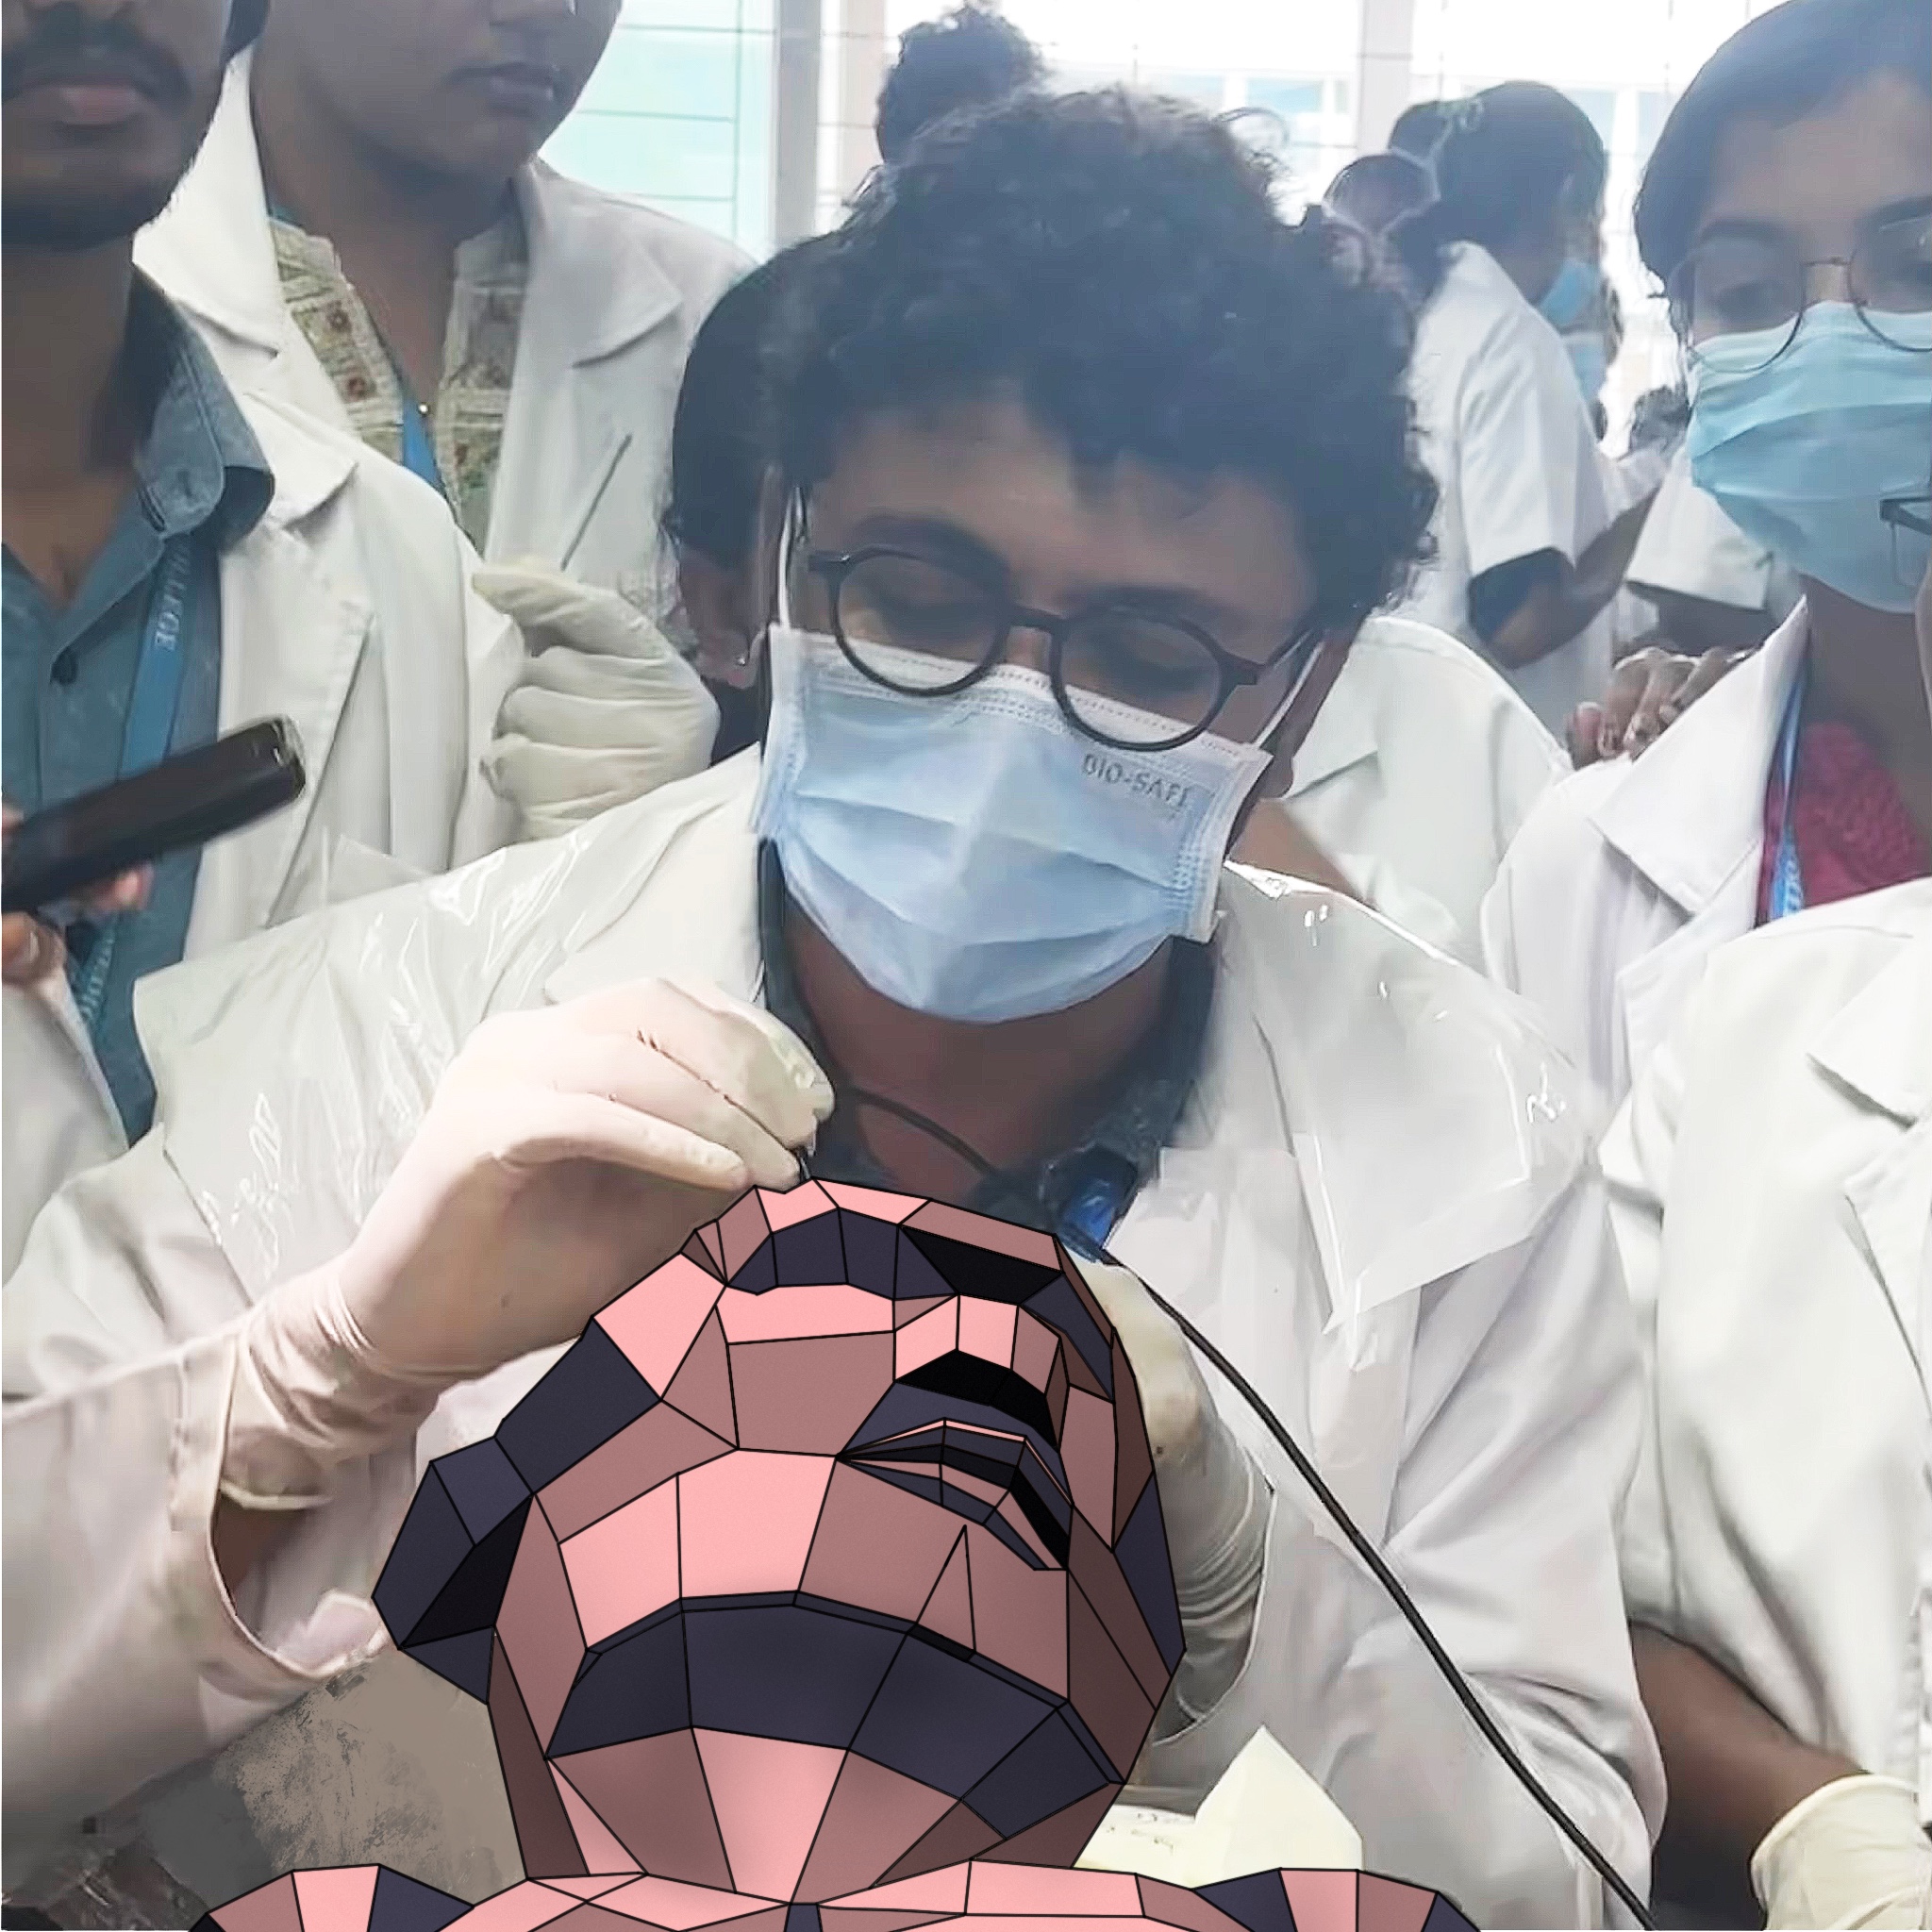

Hands-On Dissection Experience

Trained through extensive, full-body human cadaver dissection—from head to toe—Dr Daron possesses a rare, in-depth understanding of human anatomy. This foundational experience allows for the creation of highly realistic, anatomically precise medical illustrations, setting a high standard for accuracy and detail in the field